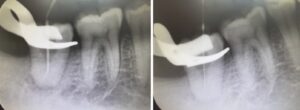

精密根管治療では、根っこの形を正確に把握するために

造影剤を使用し、レントゲンで確認しながら治療を進めています。

器具が先端までしっかり届いているかを丁寧にチェックすることで、治療の成功率を高めています。